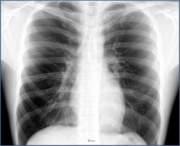

人工知能で肺結核と戦う Deep Learning/医療活用事例

肺がん診断の正確性をAIで向上 NVIDIA GPUテクノロジー/医療活用事例